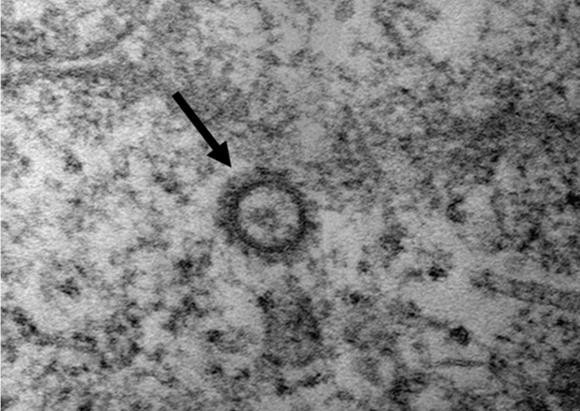

코로나19 바이러스(SARS-CoV-2)의 전자현미경 사진. ⓒ 질병관리본부